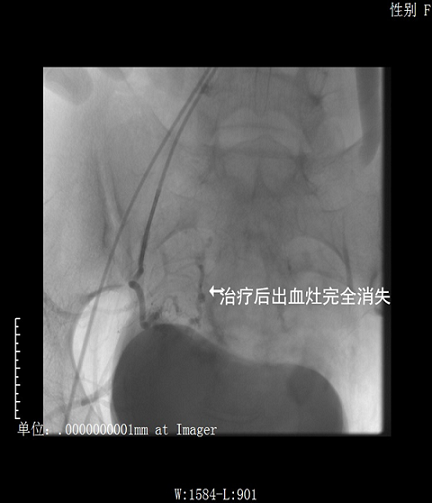

首例急诊产后子宫大出血患者在我院介入手术成功

近日,我院放射科、妇产科携手合作,采用介入技术,成功地为一名27岁的产后大出血患者实施了子宫动脉栓塞手术。此手术的成功实施在我院尚属首例。

患者陈某于外院行剖宫产术后大出血,急诊转入我院治疗。来院时患者神志萎靡、精神不振,检查示:血红蛋白55g/l且出血不止,情况危急。给予抗感染、输血及子宫收缩等对症治疗,未见明显好转。以往这种情况,为了挽救患者生命,只有切除患者的子宫。可患者年仅27岁,子宫切除将大大影响其今后的生活质量。妇产科唐华主任医师、王健主治医师立即与放射科联系,请陈应付副主任医师和赵蔚副主任医师应用介入手术解决这一难题,手术取得成功,患者子宫得以保住。